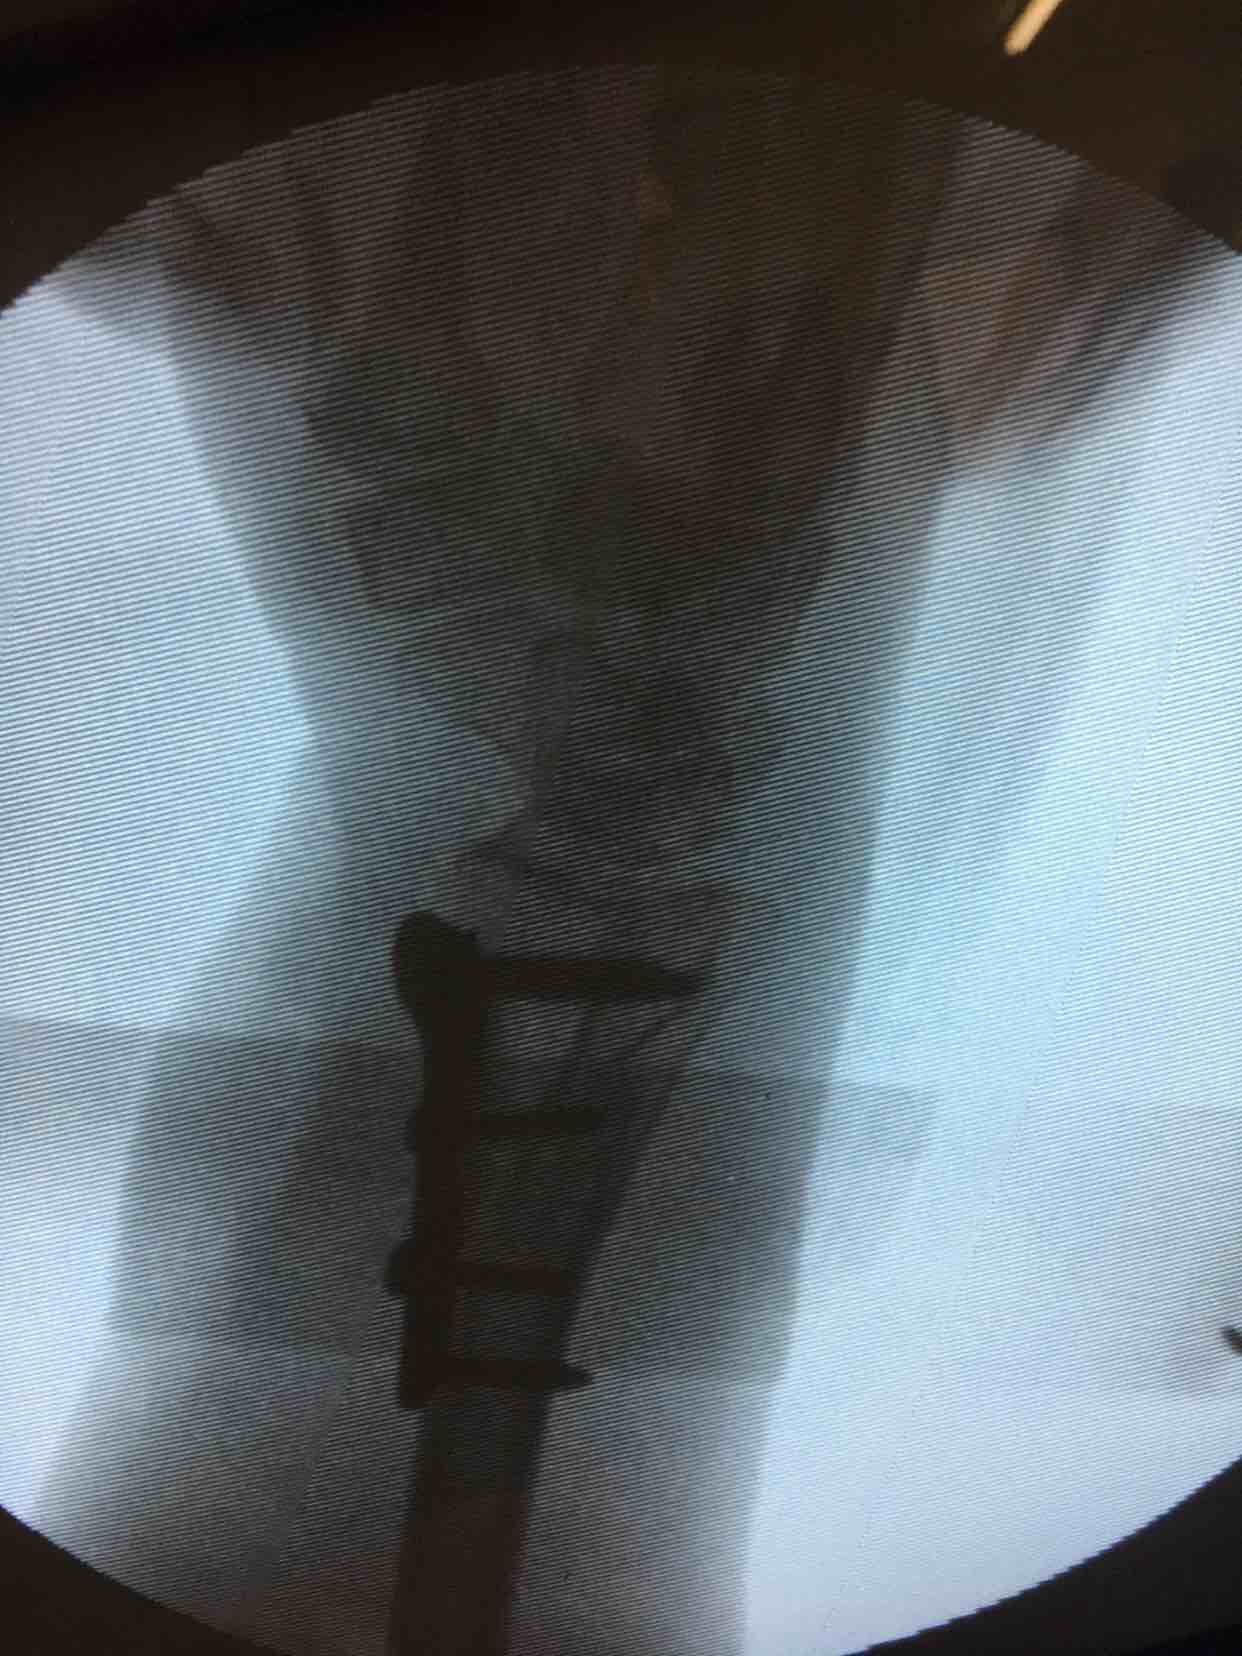

尺桡骨远端粉碎性骨折并下尺桡关节分离

诊断右尺桡骨远端粉碎性骨折并下尺桡关节分离在臂丛麻醉下行切复内固定术,术后抗炎,消肿等处理。